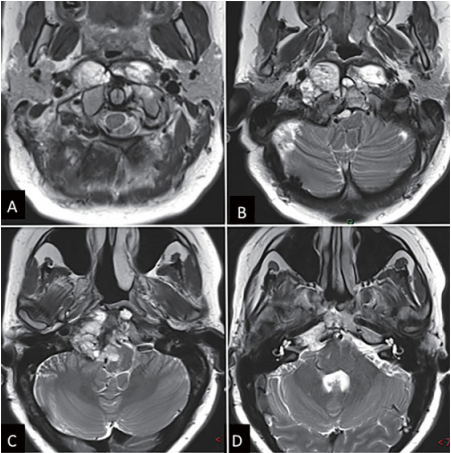

图1:鼻内镜手术前影像(A-D)MRI T2加权像显示巨大脊索瘤延伸至椎前间隙和齿状突周围。肿瘤横向侵犯舌下管和颈静脉孔,向内延伸至硬膜内间隙。肿瘤从斜坡中部扩展至枢椎齿状突周围。